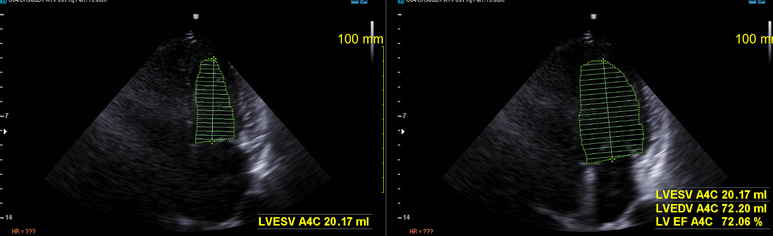

심초음파

Simpson method에서 수축기 기능 정상

경계의 좌심실비대

경도의 이첨판 역류

좌심방 확장 의심